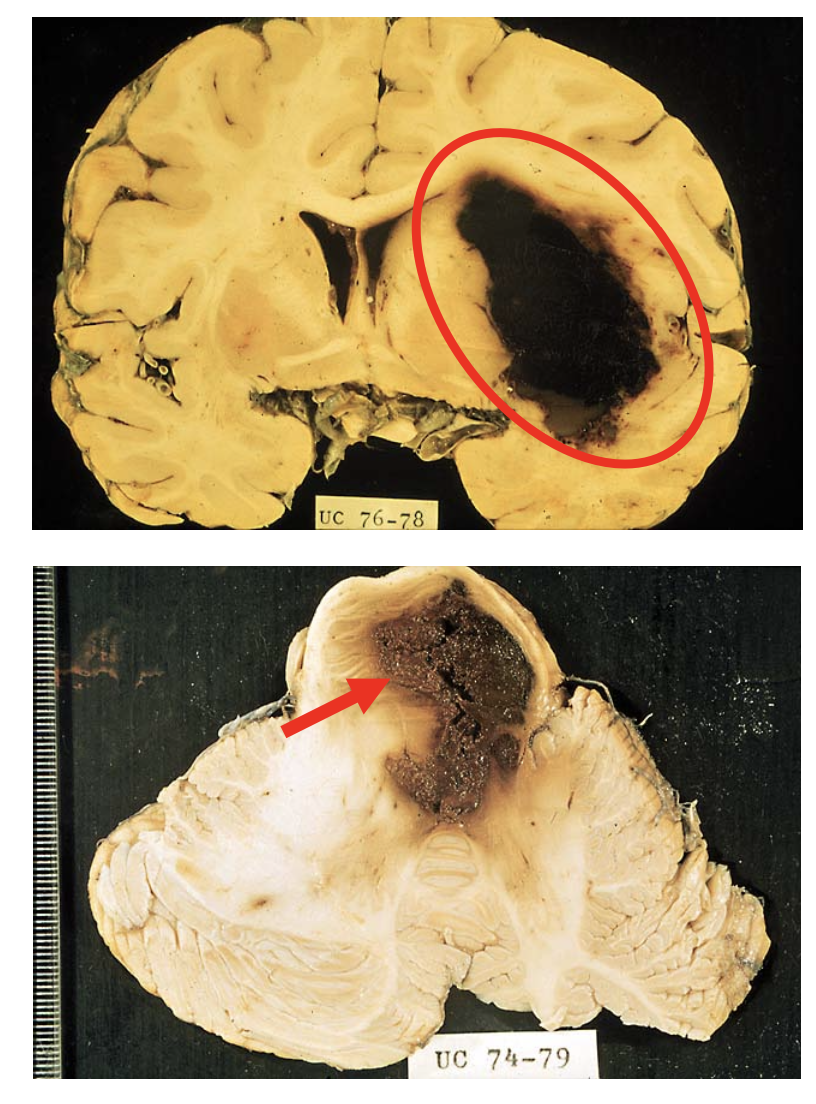

Parenchymal hemorrhage - pathology

The blood products are absorbed by macrophages and walled off by gliosis.

Months later, the cystic cavity appears tan - brown from hemosiderin-laden macrophages.